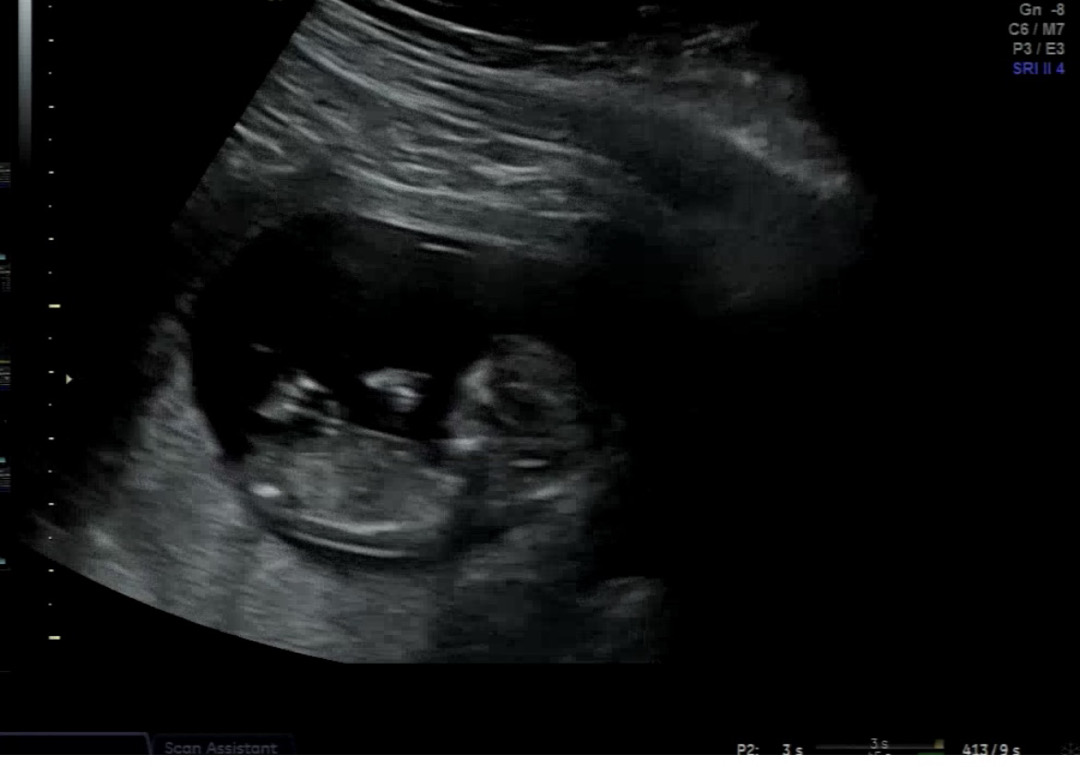

오늘 12주 기형아검사 하고 왔는데 성별 너무 궁금해요 병원 초음파기계 화질이 별로라 잘 안보이는데 고수분들 부탁드립니당 ...!!!!

각도가 평평해보이는게 딸같아요!

딸일거같아요!!